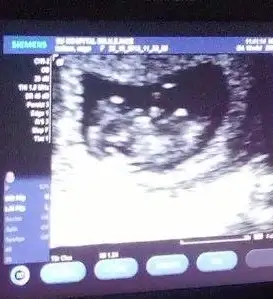

Merhaba kızlar.biz de 12+1 haftalığız.benim ultrason sonucuma da bakabilir misiniz?Eki Görüntüle 857572 Eki Görüntüle 857571

bana kiz gibi geldi ilk resimde :)